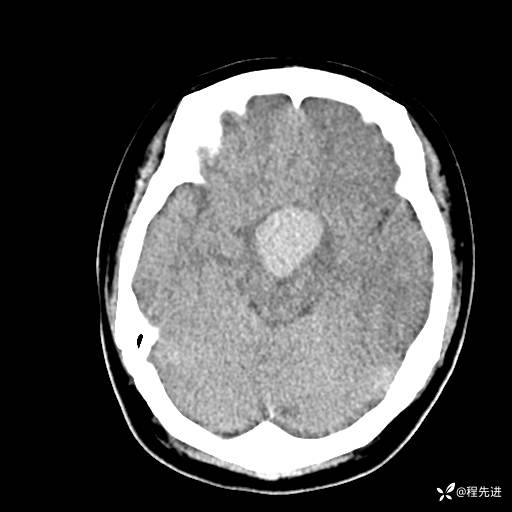

CT平扫: